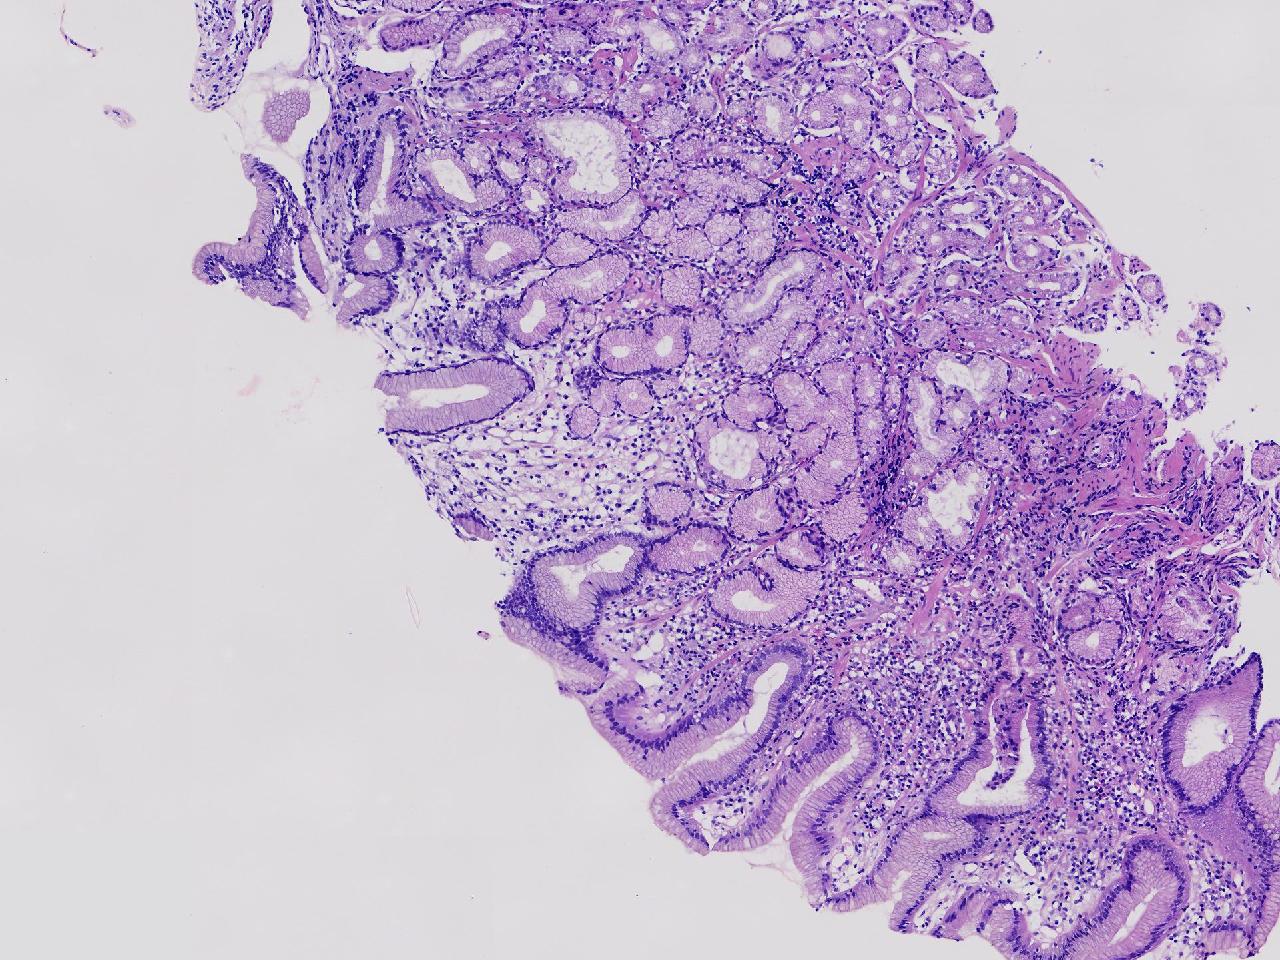

男,76岁。胃体前壁见1纵行溃疡,底覆白苔,周围粘膜充血水肿,于病变周边取材3块。

胃体前壁活检

灰白色不整形软组织3块,直径均0.2厘米。

图2

粘膜中度慢性炎伴糜烂,固有层淋巴细胞聚集